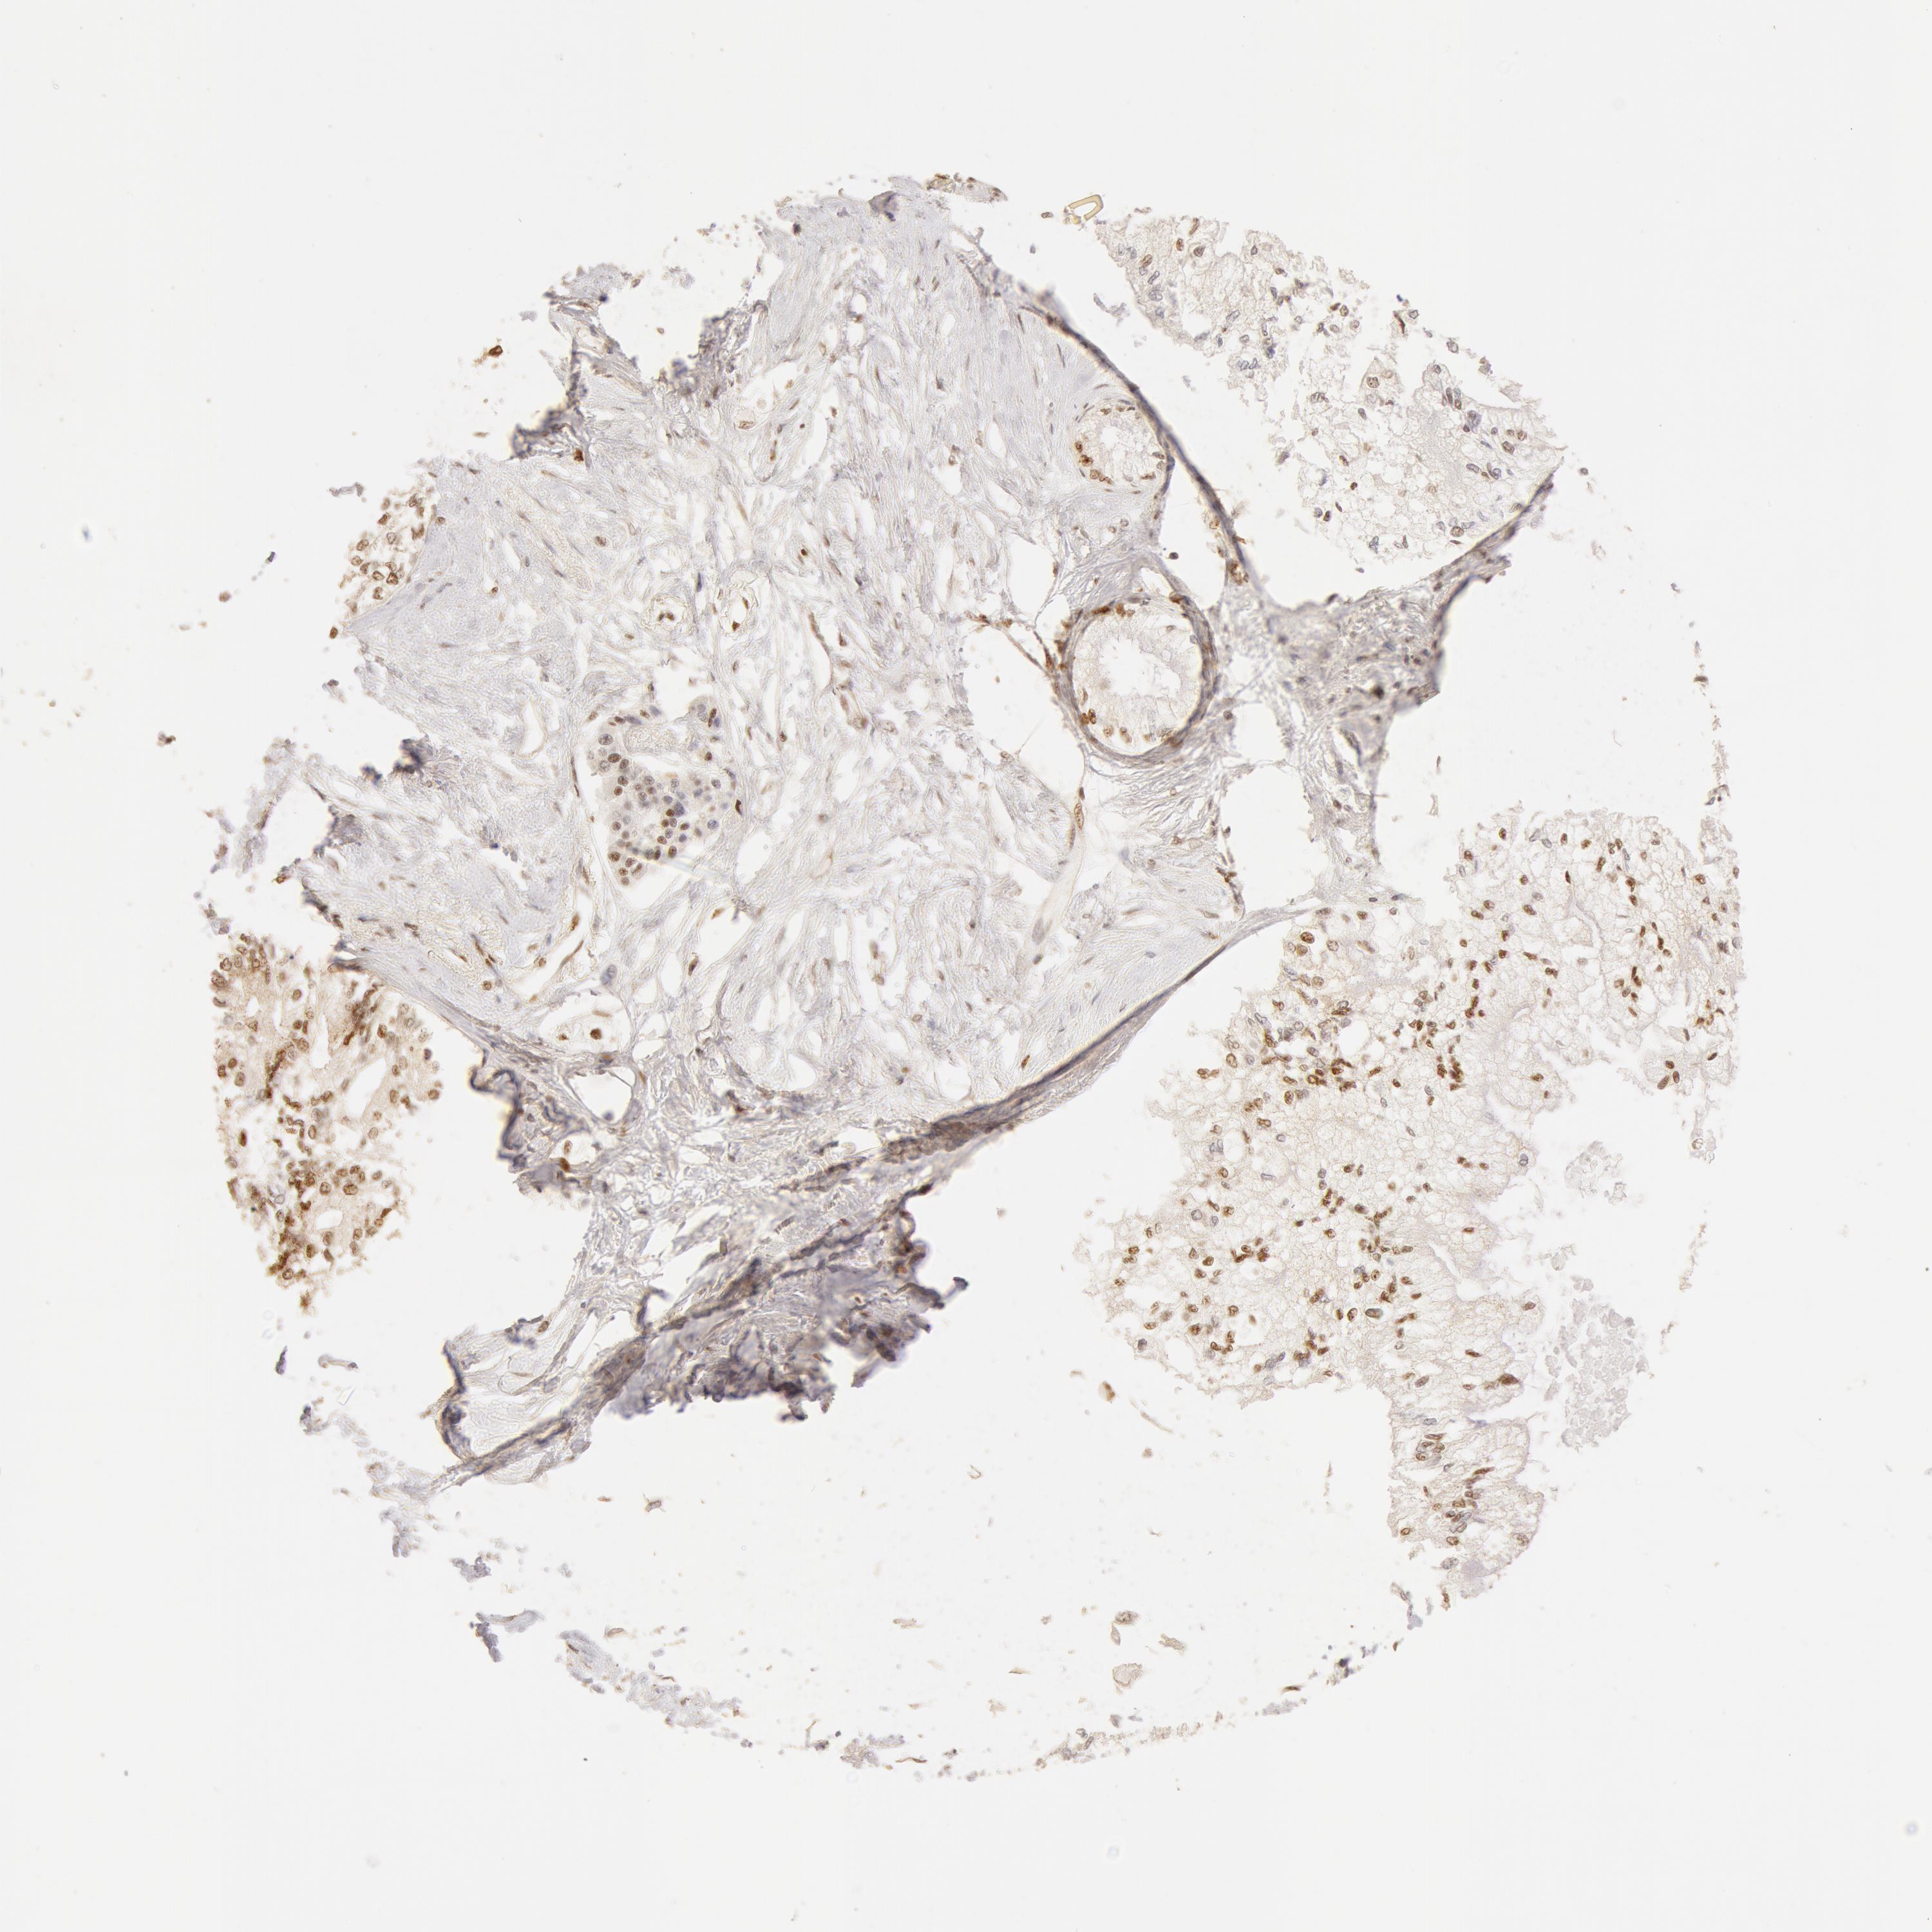

PANCREATIC CANCER - Protein expressioni

A mouse-over function shows sample information and annotation data. Click on an image to view it in a full screen mode. Samples can be filtered based on level of antibody staining by selecting one or several of the following categories: high, medium, low and not detected. The assay and annotation is described here.

Note that samples used for immunohistochemistry by the Human Protein Atlas do not correspond to samples in the TCGA dataset.

Antibody stainingi

Antibody staining in the annotated cell types in the current human tissue is reported as not detected, low, medium, or high, based on conventional immunohistochemistry profiling in selected tissues. This score is based on the combination of the staining intensity and fraction of stained cells.

Each image is clickable and will lead to virtual microscopy that enables deeper exploration of all samples and also displays staining intensity scores, fraction scores and subcellular localization as well as patient and tissue information for each sample.

Antibody HPA042050

Antibody HPA043516

Antibody CAB001718

Adenocarcinoma, NOS